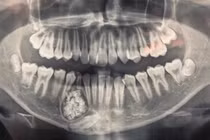

Khi chỉ định chụp X-quang, bác sĩ phát hiện xương hàm dưới có khối u răng kích cỡ 3x4 cm, bên trong chứa nhiều răng to, nhỏ có đầy đủ tổ chức như rằng bình thường, kết lại thành một khối.

| Khối u răng của nam bệnh nhân chứa đầy răng to, nhỏ phía trong. |